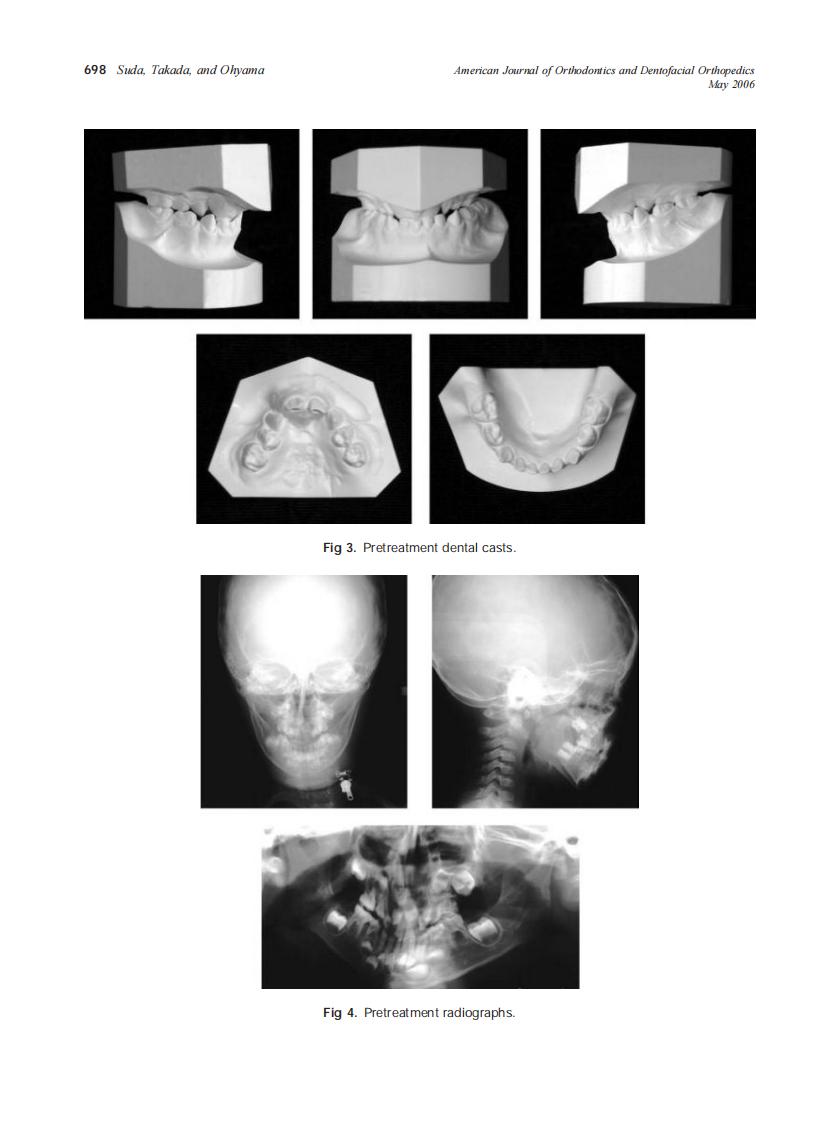

2006_129_5_696_705_Suda.pdf